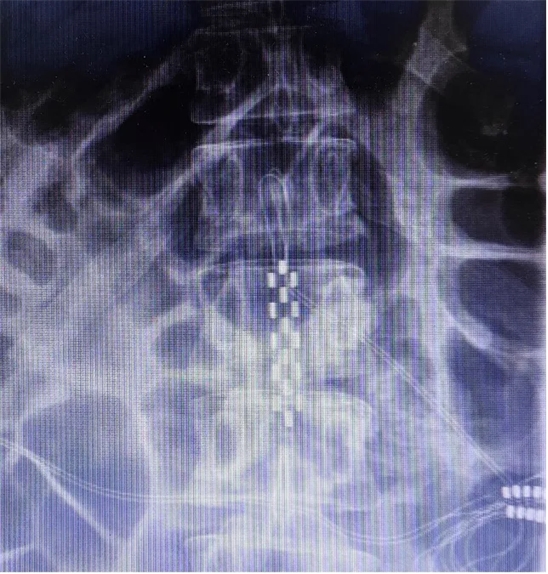

患者長期以來歷經(jīng)康復理療及藥物對癥治療,未見明顯療效,病情仍持續(xù)進展,此次專程為尋求脊髓電刺激神經(jīng)調控治療就診。入院后神經(jīng)調控專業(yè)組團隊結合文獻報道的相關治療經(jīng)驗,并經(jīng)過充分的討論,同意實施脊髓電刺激治療,以改善病人共濟失調步態(tài)及平衡障礙。2024年11月20日,夏小雨主任團隊為患者實施了胸腰段脊髓電刺激電極植入手術(SCS1期),在術中影像和術中電生理的保障下,1根5-6-5觸點電極被準確植入到T12-L1硬膜外。

解放軍總醫(yī)院神經(jīng)外科醫(yī)學部派駐第七醫(yī)學中心神經(jīng)外科夏小雨副主任醫(yī)師指出,遺傳性脊髓小腦共濟失調是一組由基因變異引起的以脊髓和小腦損害為主要臨床表現(xiàn)的常染色體顯性遺傳的神經(jīng)退行性疾病。2018年5月被納入中國第一批罕見病目錄。目前尚無能有效阻止或減緩SCA進展的治療方法。目前我們團隊將脊髓電刺激(SCS)手術視作一種有效的對癥治療的外科調控手段,它對于疼痛、痙攣、缺血和步態(tài)障礙的改善尤其突出、引人注目。國內SCA患者接受SCS治療后的長期隨訪有效率令人鼓舞,我們團隊也進行了積極的開展。目前,針對步態(tài)障礙的控制,SCS電極靶點的位置尚無統(tǒng)一的方案。相較于此前報道較多的T9-11硬膜外,本病例中我們電極埋置的位置相對更低,更接近于腰膨大的末端位置,同樣取得了很好的療效,這個位置主要還是根據(jù)術中電生理的結果來確定的。除了脊髓小腦共濟失調,我們團隊也開展了針對帕金森凍結步態(tài)、腦卒中后步態(tài)障礙等其他情況的脊髓電刺激治療,均取得了滿意的效果,積累了豐富的經(jīng)驗。